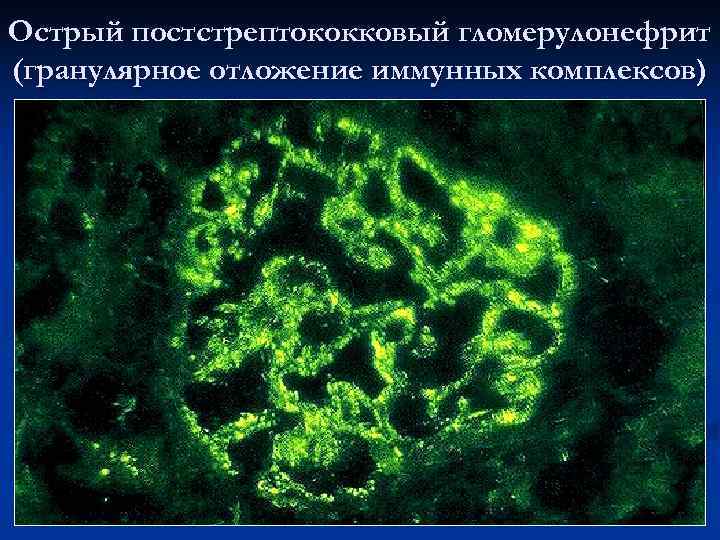

Симптомы подострого гломерулонефрита: фото и описание